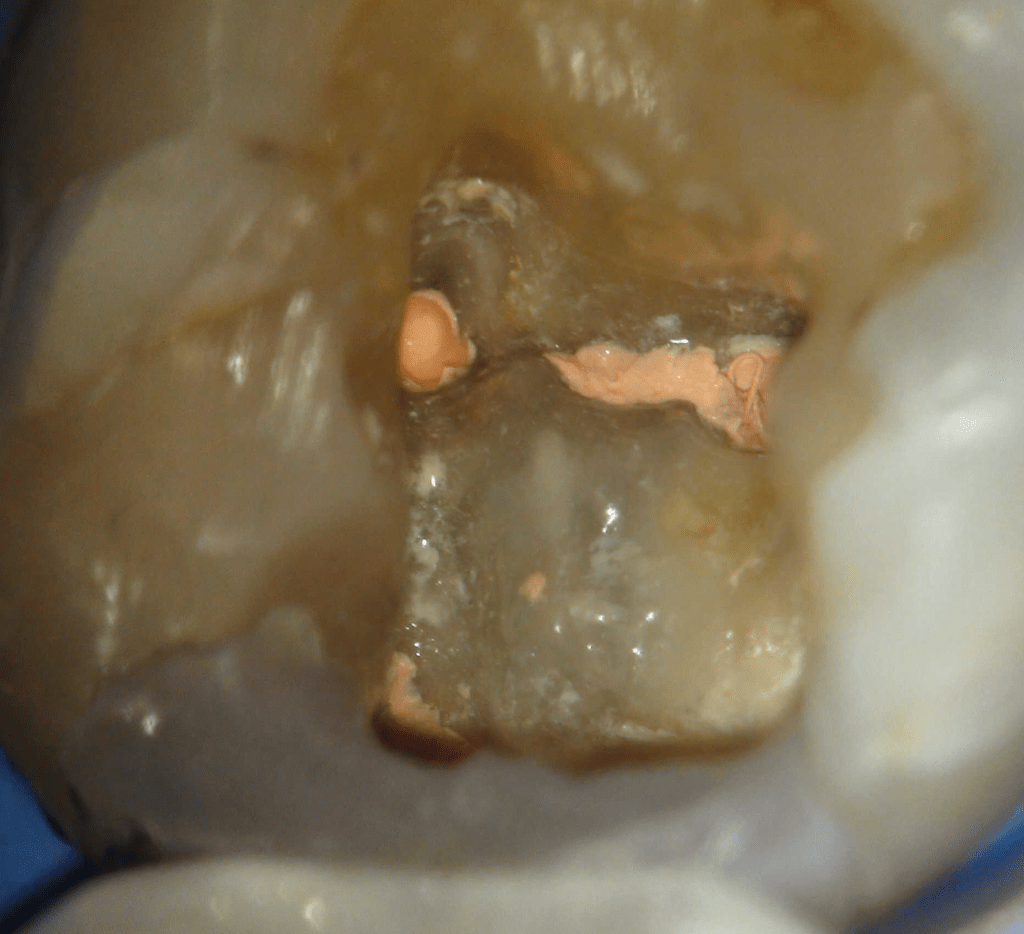

Reconstrucción preendodóntica

Reco pared vesticular

Reco pre-endo, molar inferior

Reco preendo + 4 conductos molar superior

Reco preendo, 2o Molar superior